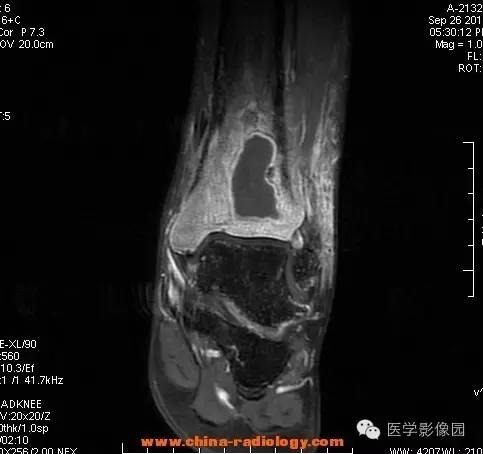

影像学表现:胫骨中下段干骺端不未规则形长T1长T2信号,T2WI见不完整环形稍低信号影,T2脂肪抑制低信号更明显,并见胫骨下段及踝关节后外侧软组织呈弥漫稍高信号,增强明显不均匀强化,增强见低信号环内有环形强化影。

影像学表现:表现为长骨干骺端有椭圆形密度减低区,边缘有清晰的骨质硬化,病变与邻近正常骨髓腔境界清楚。MRI上T1WI呈低信号,少数呈等信号,T2WI多为混杂高信号,增强扫描可见环状强化,强化的脓肿壁薄而均匀。